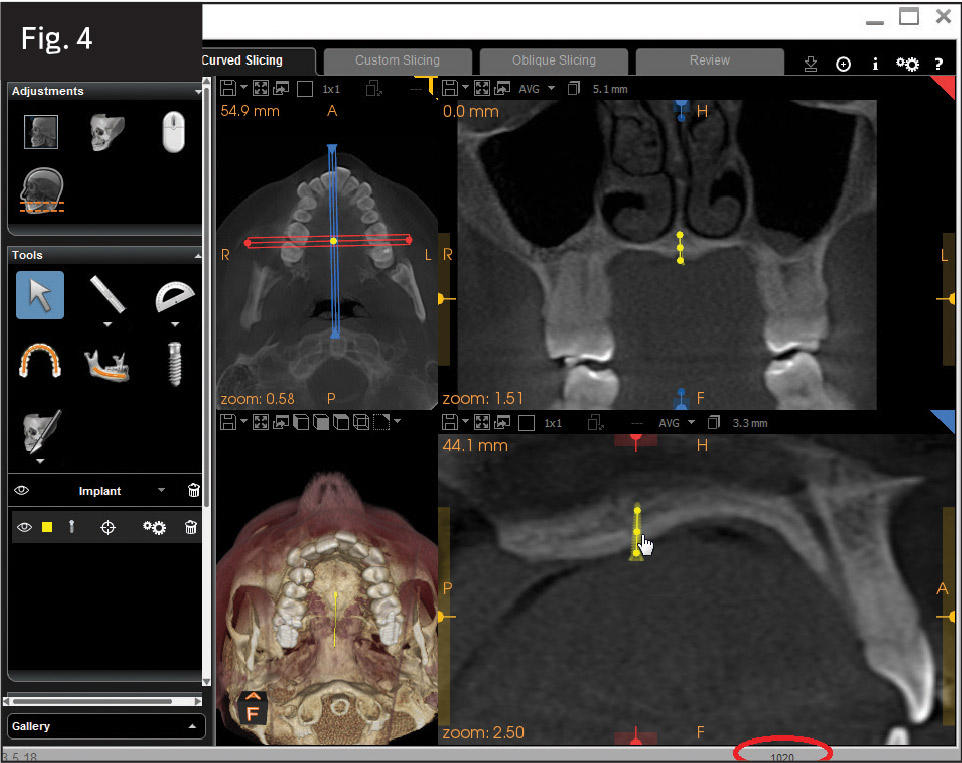

4. A collimated cone-beam computed tomography (CBCT) image of the palate and 3-D imaging software allow the clinician to make a careful assessment of the midpalatal suture or the immediately adjacent paramedian locations by performing a simulation (Fig. 4). Both quality and quantity of bone can be assessed, giving the clinician confidence in the intended insertion site. (I use Carestream Dental's CS 9300 system and CS 3D Imaging software.)

In Case 1, a collimated CBCT view of the maxilla was captured with a Carestream Dental CS 9300. A miniscrew placement simulation was performed, showing excellent bone density at the midpalatal suture, allowing for a single miniscrew and dumbbell (see Fig. 4). In Case 2, a similar simulation was also performed; both quality and quantity of bone were assessed. It was determined that a single midpalatal miniscrew at the midpoint of the suture would be less reliable than two paramedian miniscrews. The density-gradient tools of the miniscrew placement simulation showed an acceptable gradient of relative bone density in two paramedian locations, rather than a single screw placed in the midpalate.